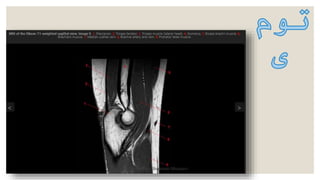

‫نرم‬ ‫بافت‬ ‫و‬ ‫مفصل‬ ،‫استخوان‬ ‫تومور‬